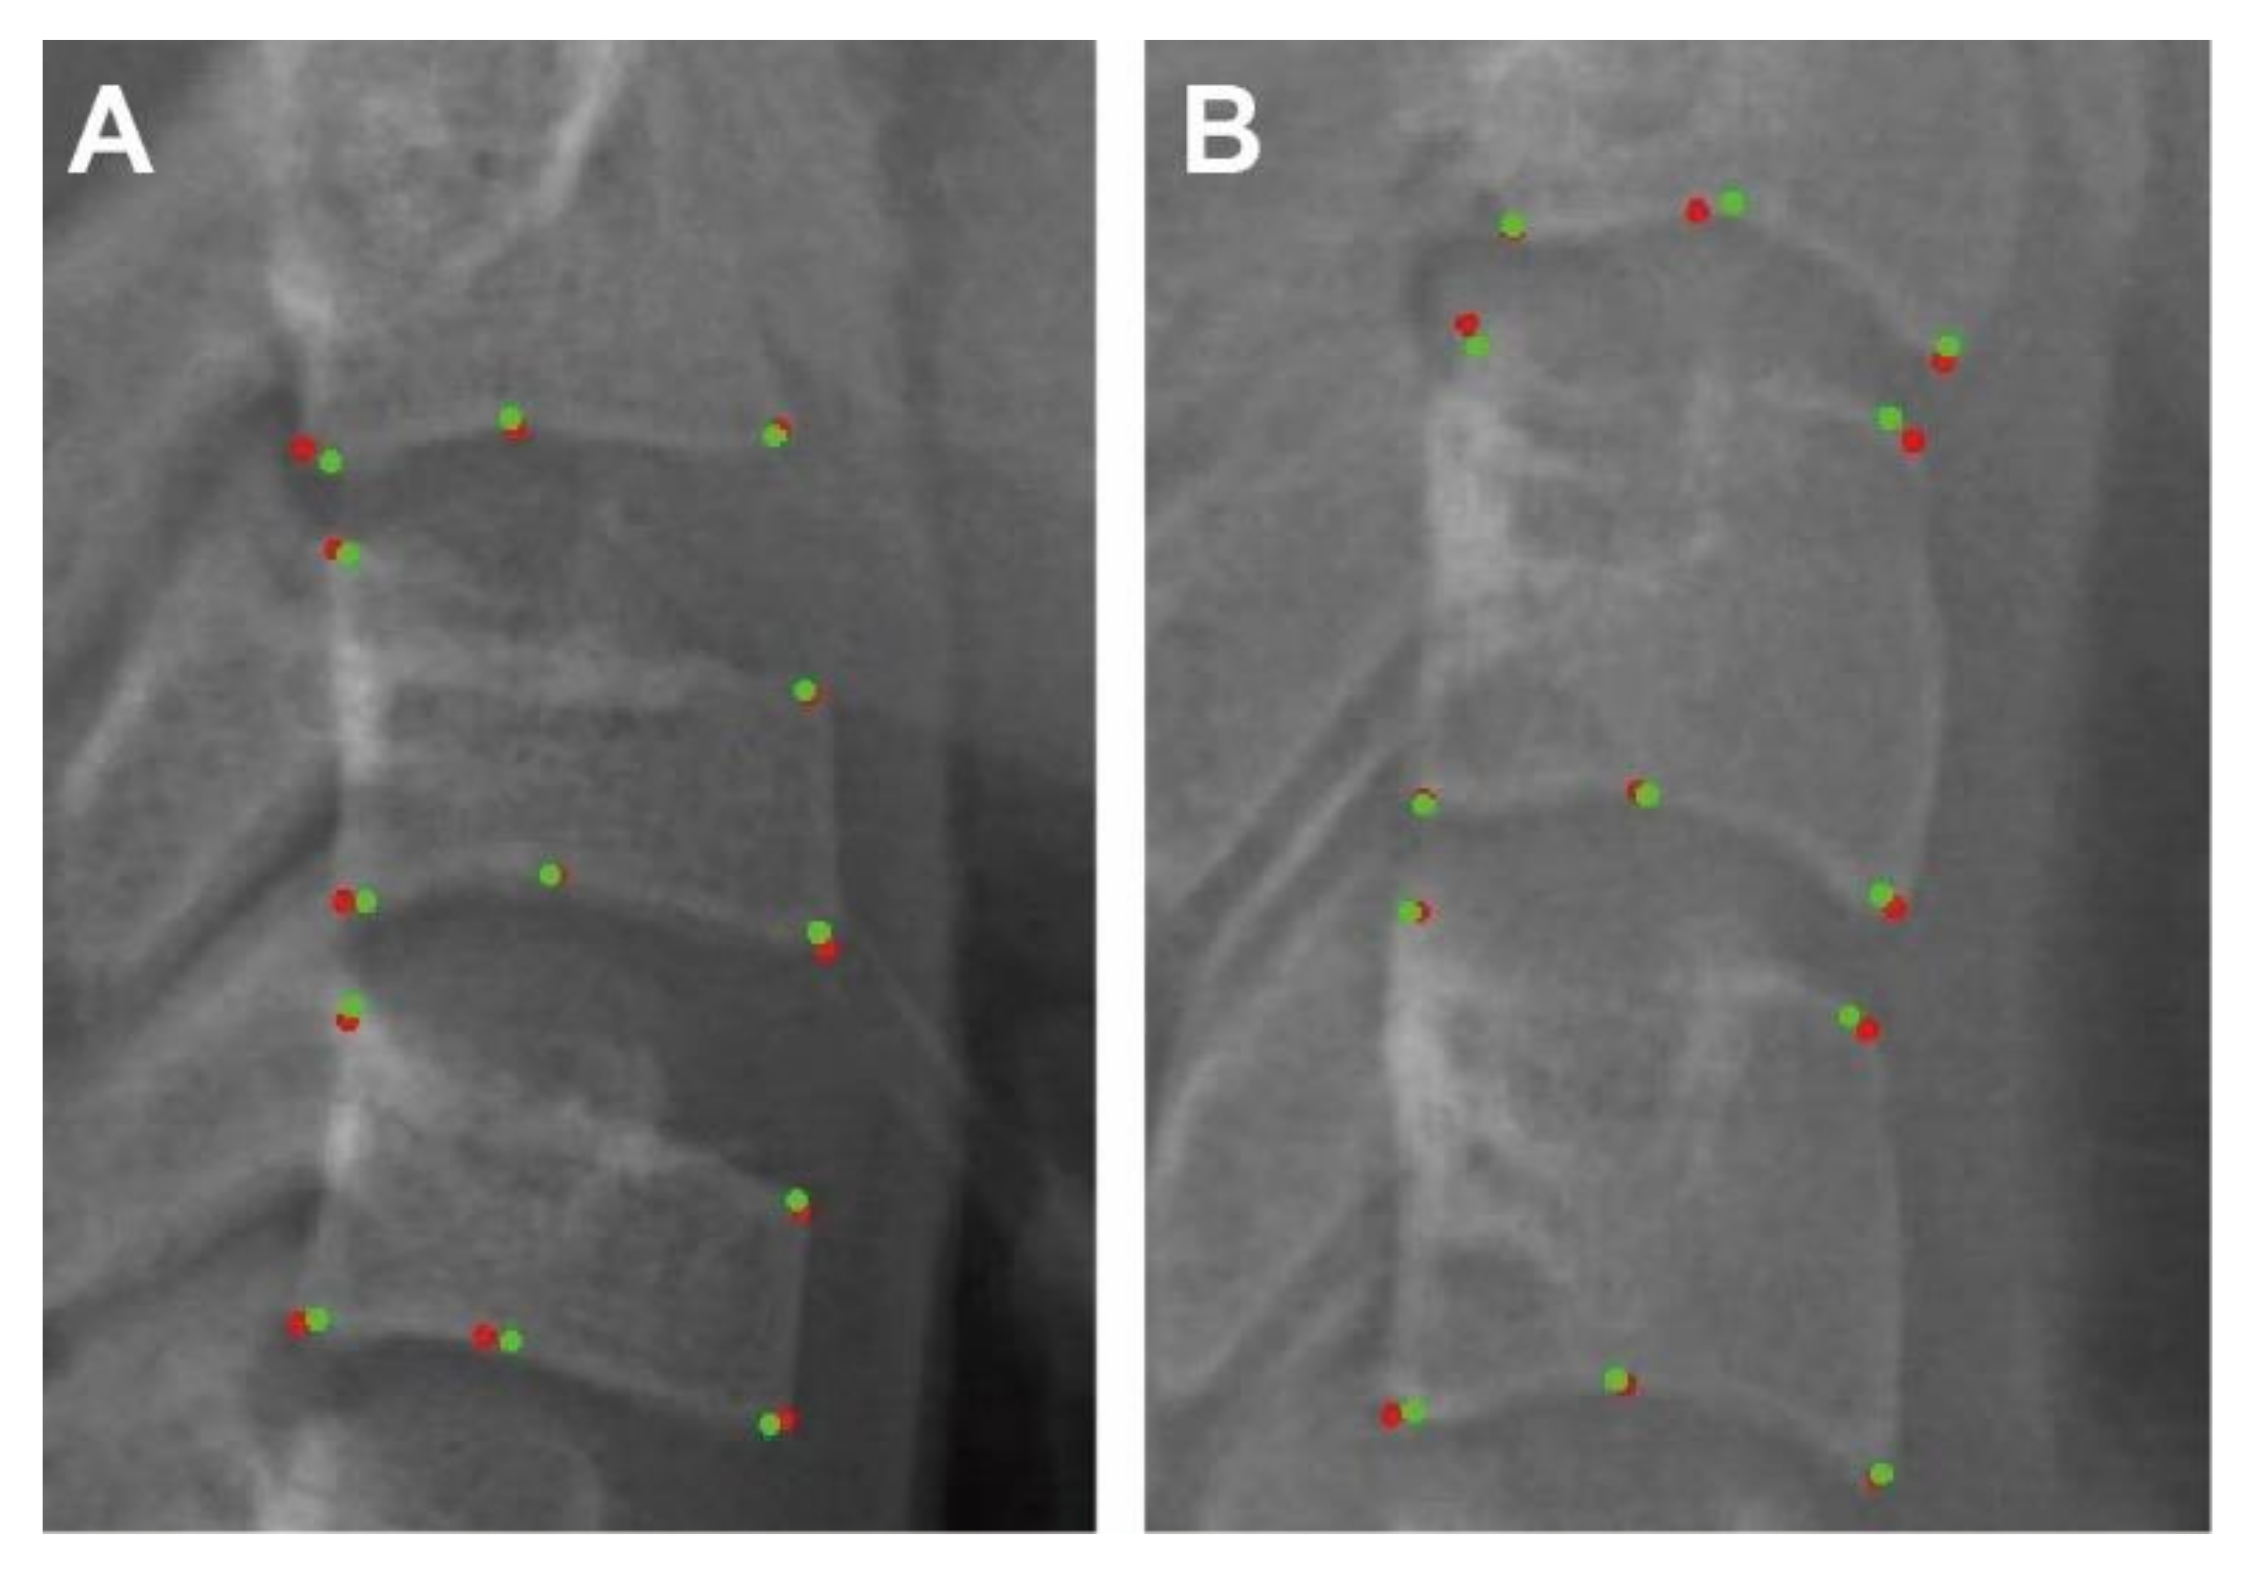

3.1. Evaluation of Labelling

| Landmarks/ Measurements | Definition |

|---|---|

| C2lp | The most posterior point of C2 on the lower border |

| C2la | The most anterior point of C2 on the lower border |

| C2m | The deepest point of the concavity at the lower border of C2 |

| C2Conc | The distance between C2m and the line connecting C2lp and C2la |

| C3up | The most posterior point of C3 on the upper border |

| C3ua | The most anterior point of C3 on the upper border |

| C3lp | The most posterior point of C3 on the lower border |

| C3la | The most anterior point of C3 on the lower border |

| C3m | The deepest point of the concavity at the lower border of C3 |

| C3Conc | The distance between C3m and the line connecting C3lp and C3la |

| C3BAR | Ratio between the length of the base (distance C3lp − C3la) and the anterior height (distance C3ua − C3la) of the body of C3. |

| C4up | The most posterior point of C4 on the upper border |

| C4ua | The most posterior point of C4 on the upper border |

| C4lp | The most posterior point of C4 on the lower border |

| C4la | The most anterior point of C4 on the lower border |

| C4m | The deepest point of the concavity at the lower border of C4 |

| C4Conc | The distance between C4m and the line connecting C4lp and C4la |

| C4BAR | ratio between the length of the base (distance C4lp − C4la) and the anterior height (distance C4ua − C4la) of the body of C4 |